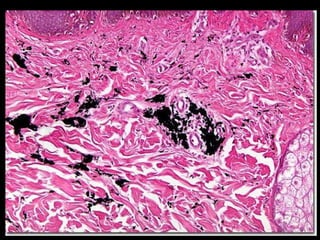

Calcificações Patológicas Distrófica Metastática

Calcificação Distrófica Lesão Tecidual Degeneração Necrose Perda da proteção osmótico/coloidal da célula Precipitação de sais de Ca

Calcificação Distrófica LesãoTecidual Degeneração Necrose Perda da proteção osmótico/coloidal da célula Precipitação de sais de Ca